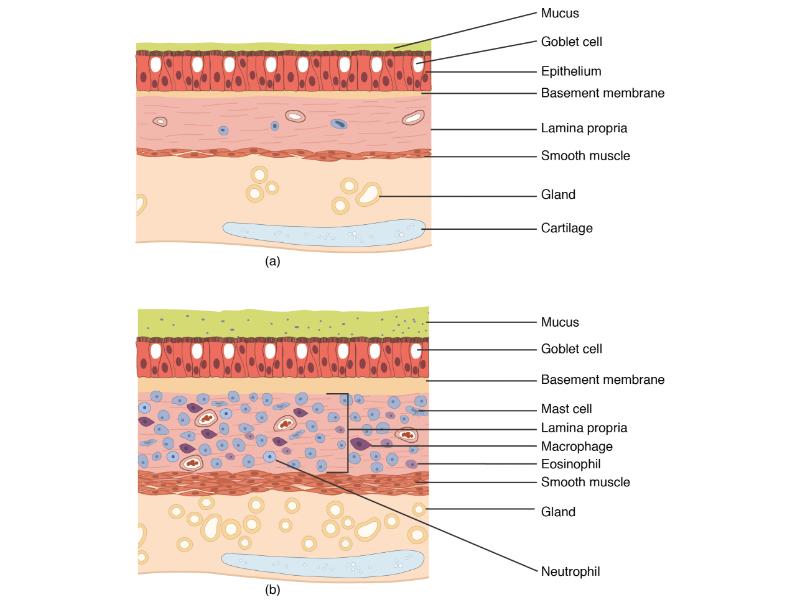

Respiratory epithelium

- Pseudostratified

- Ciliated

- Columnar

- Epithelium with

- 4 Cells

- Ciliated columnar cells

- Non-ciliated columnar cells

- Goblet cells

- Basal cells

Trachea

Bronchi - Transitions

- Intrapulmonary bronchi

- Irregular cartilage

- Respiratory epithelium

- Glands

- Bronchioles

- Smooth muscle REPLACE cartilage

- Ciliated columnar > Ciliated cuboidal

- NO glands - goblet cells -> secretory cells